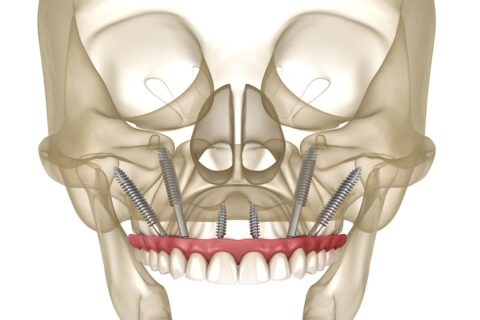

Zygomatic implants, also known as Zygoma implants, are an alternative to bone grafting techniques for the upper jaw and offer a viable option for individuals who desire dental implants but are severely deficient in upper jaw bone. These implants are inserted into the zygomatic bone (cheekbone) to support dentures, bridges, and upper jaw (maxillary) teeth, in contrast to traditional “root form” dental implants that are implanted into the jaws to replace teeth.

They pass transversely through the weak area of the upper jaw and attach to the bottom of the cheekbones via your sinuses.